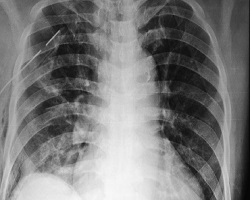

Диференцијална дијагноза: Мада је пнеумоторакс етиогенетски, клинички и РТГ добро познато патолошко стање, честе су погрешне дијагнозе или диференцијално дијагнозне заблуде. Тешкоће при препознавању спонтаног пнеумоторакса и других по клиничкој симптоматологији и морфолошком изгледу сличним плеуропулмоналних обољења, настају при малим физички тешко препознатљивим и РТГ уочљивим количинама ваздуха и течности у плеуралној дупљи. Разлог су и неуки физички и РТГ прегледи, погрешно тумачење клиничких симптома и знакова болести.